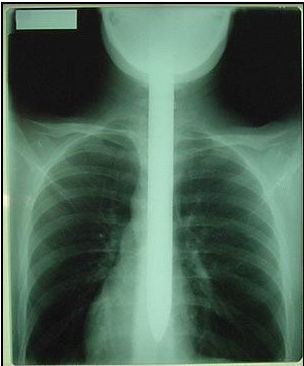

まずは、正面から↓

sword_x3.jpg

どの辺りまで飲み込んでいるのでしょうか…。